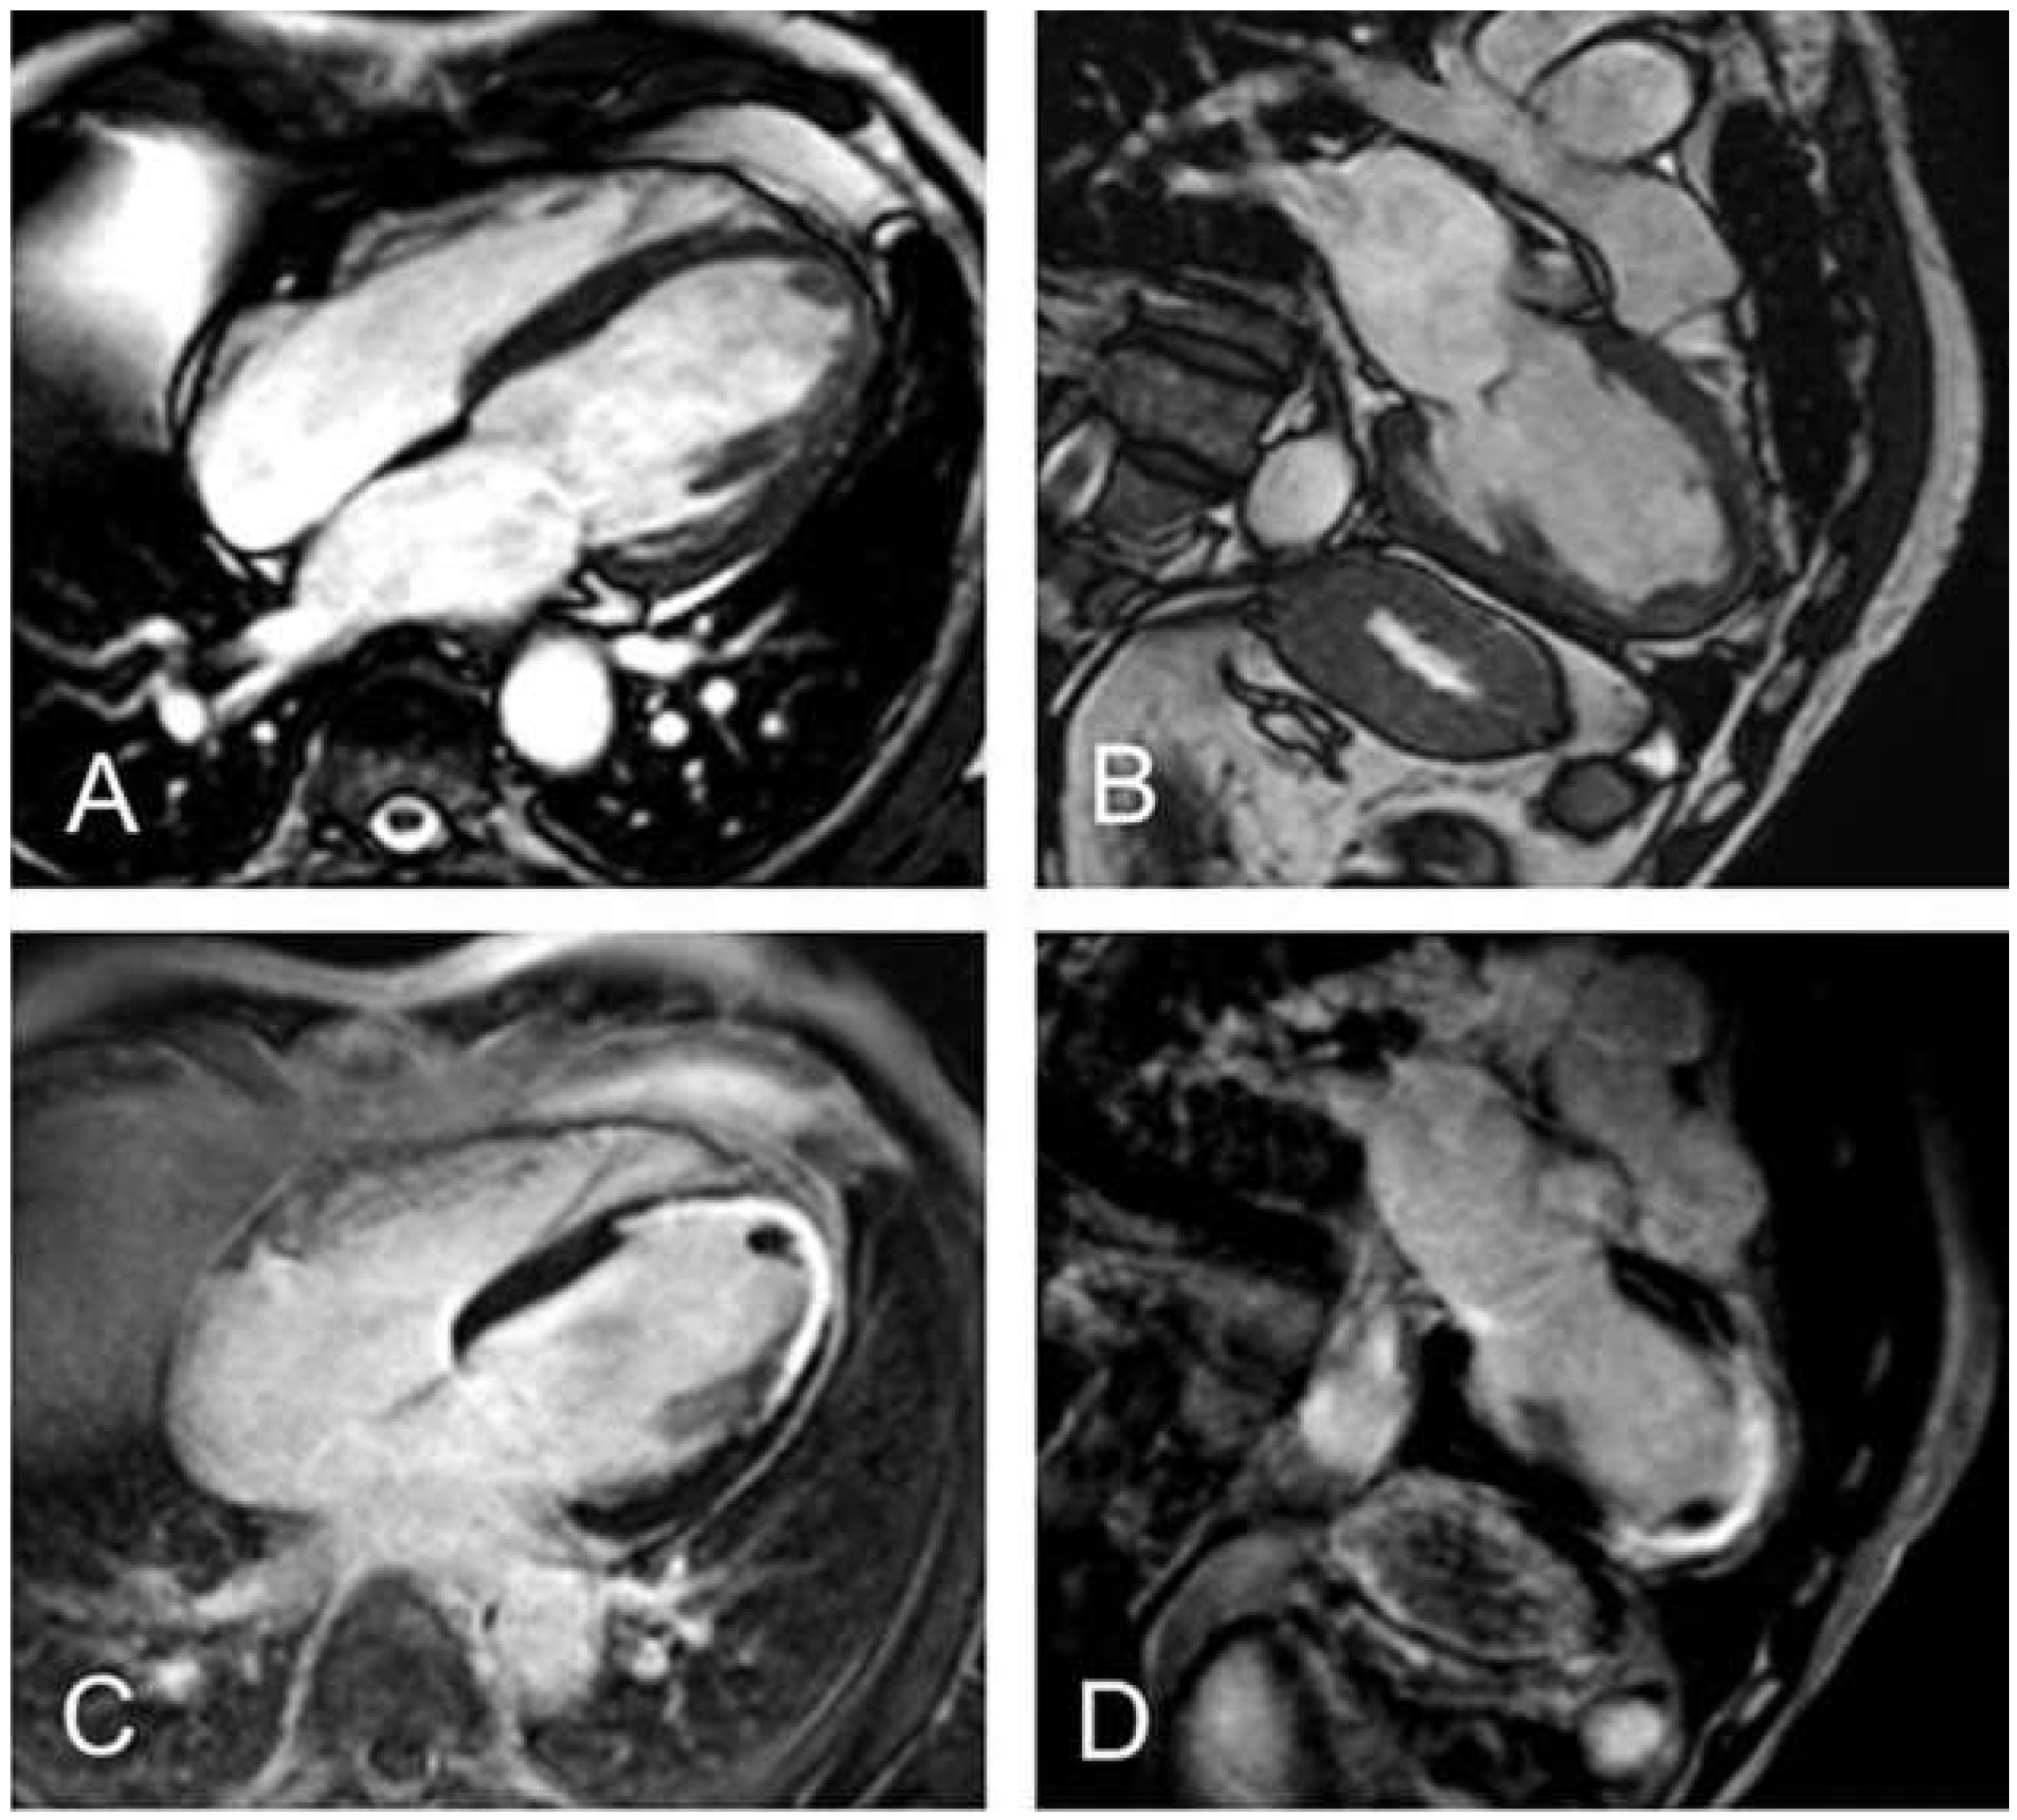

Durch den Verschluss eines Koronargefässes und der daraus resultierenden Sauerstoffunterversorgung des Myokards kommt es zu einem myokardialen Zellschaden, der unterschiedlich zur Darstellung kommt. Im Einzelnen kann Periinfarktzone, mikrovaskuläre Obstruktion (MVO) oder intramyokardiale Hämorrhagie (IMH) auftreten. Diese Entitäten haben unterschiedliche prognostische Bedeutung. Die Periinfarktzone wird als Substrat für potentiell lebensbedrohliche rhythmogene Ereignisse verantwortlich gemacht. Im LGE stellt sie sich mit intermediärer Intensität um das zentrale, infarzierte Gewebe dar. Die Grösse der Periinfarktzone ist ein unabhängiger Prädiktor für Mortalität nach Myokardinfarkt [69].

Nach erfolgreicher Revaskularisation kann es durch Auftreten eines Ödems (Figure 6A) und dadurch bedingte Kompression der Kapillaren, Aktivierung von Neutrophilen und Thrombozyten im Infarktgewebe, Mikroembolisation von atherosklerostischem Material nach Koronarintervention und Nekrose von Kapillaren zur Ausbildung von MVO kommen [70]. Die MVO stellt sich in den LGE-Aufnahmen als dunkles Areal im Zentrum eines Infarktes umgeben von deutlich helleren Arealen dar (Figure 6B) und ist ein starker Prädiktor für ungünstiges myokardiales Remodelling, das Ausbilden einer eingeschränkten LV-Funktion und den kombinierten Endpunkt aus Tod, nicht tödlichem Reinfarkt und Herzinsuffizienz [71,72].

Wenn prolongierte Ischämie zum Verlust der kapillaren Endothelzellintegrität führt, kann nach Reperfusion durch Extravasation von Erythrozyten eine IMH auftreten. Diese stellt sich in T2-gewichteten Aufnahmen als hypointense Areale im infarzierten Myokardgewebe dar. Auch diese Entität ist mit einer eingeschränkten linksventrikulären Funktion und einer erhöhten Rate an major adverse cardiovascular events (MACE) nach einem Myokardinfarkt assoziiert [73]. Prinzipiell reversibel ist das ischämiebedingte myokardiale Ödem, das sich in T2-gewichteten Aufnahmen hyperintens darstellt. Legt man diese, in den T2- gewich te ten Aufnahmen, hyperintensen Areale zugrun de, kann durch Subtraktion der irreversibel ge schädigten Areale (hyperintense Areale in den LGEAufnahmen) der Anteil myokardialen Gewebes bestimmt werden, der sich nach einem Infarkt erholen kann. Die Grösse dieses Parameters korreliert invers mit der Zeit, die bis zur Reperfusion benötigt wurde, und ist ein starker Prädiktor für die Prognose nach akutem Myokardinfarkt [74].

Figure 6. (A) zeigt eine midventrikuläre Kurzachsenschicht des linken Ventrikels in T2-gewichteter Aufnahmetechnik. Das Ausmass des myokardialen Ödems entspricht den (inferioren und lateralen) hyperintensen Myokardsegmenten. Die Late-gadolinium- enhancement(LGE)-Aufnahme, ebenfalls in Kurzachsenorientierung in (B), zeigt ein transmurales LGE in den infarzierten Myokardsegmenten und zusätzlich dunkle subendokardial gelegene Regionen, die einer mikrovaskulären Obstruktion (MVO) entsprechen.